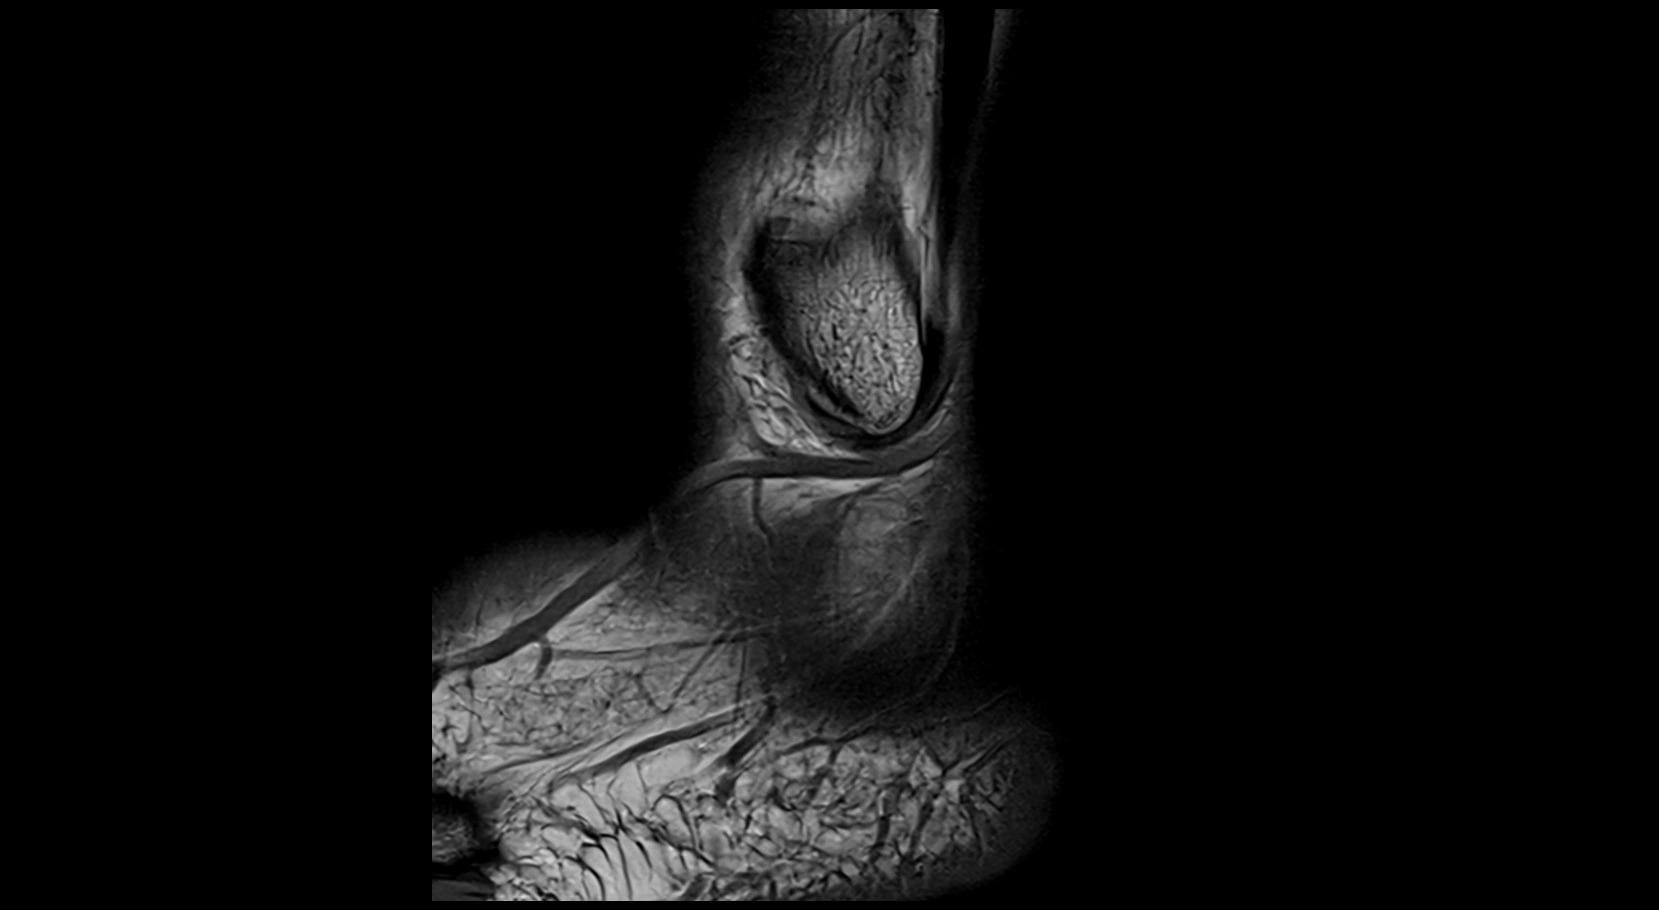

MRI image

image